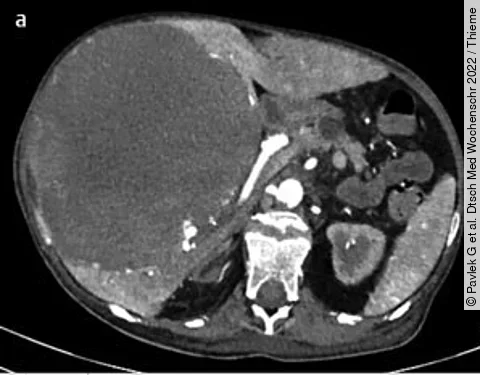

QuizAuflösung: 57-jährige Patientin mit Oberbauchschmerzen und Anämie

Befunde

Siehe großes Bild unten

1. Eine große fokale hypodense Leberläsion, welche die ganze rechte Leber einnimmt

2. Eine gute Vaskularisierung der Leberläsion

3. Computertomografisch zeigen sich Areale verschiedener Dichte innerhalb der Läsion